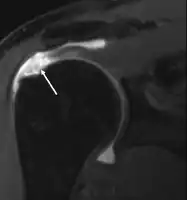

MRI

Magnetic resonance imaging (MRI) and ultrasound[46] are comparable in efficacy and helpful in diagnosis, although both have a false positive rate of 15–20%.[47] MRI can reliably detect most full-thickness tears, although very small pinpoint tears may be missed. In such situations, an MRI combined with an injection of contrast material, an MR-arthrogram, may help to confirm the diagnosis. It should be realized that a normal MRI cannot fully rule out a small tear (a false negative) while partial-thickness tears are not as reliably detected.[48] While MRI is sensitive in identifying tendon degeneration (tendinopathy), it may not reliably distinguish between a degenerative tendon and a partially torn tendon. Again, magnetic resonance arthrography can improve the differentiation.[48] An overall sensitivity of 91% (9% false negative rate) has been reported, indicating that magnetic resonance arthrography is reliable in the detection of partial-thickness rotator cuff tears.[48] However, its routine use is not advised, since it involves entering the joint with a needle, with the potential risk of infection. Consequently, the test is reserved for cases in which the diagnosis remains unclear.

Diagnostic modalities, dependent on circumstances, include X-ray, MRI, MR arthrography, double-contrast arthrography, and ultrasound. Although MR arthrography is currently considered the gold standard, ultrasound may be most cost-effective.[34] Usually, a tear will be undetected by X-ray, although bone spurs, which can impinge upon the rotator cuff tendons, may be visible.[35] Such spurs suggest chronic severe rotator cuff disease. Double-contrast arthrography involves injecting contrast dye into the shoulder joint to detect leakage out of the injured rotator cuff,[36] and its value is influenced by the experience of the operator. The most common diagnostic tool is magnetic resonance imaging (MRI), which can sometimes indicate the size of the tear, as well as its location within the tendon. Furthermore, MRI enables the detection or exclusion of complete rotator cuff tears with reasonable accuracy and is also suitable for diagnosing other pathologies of the shoulder joint.[37]